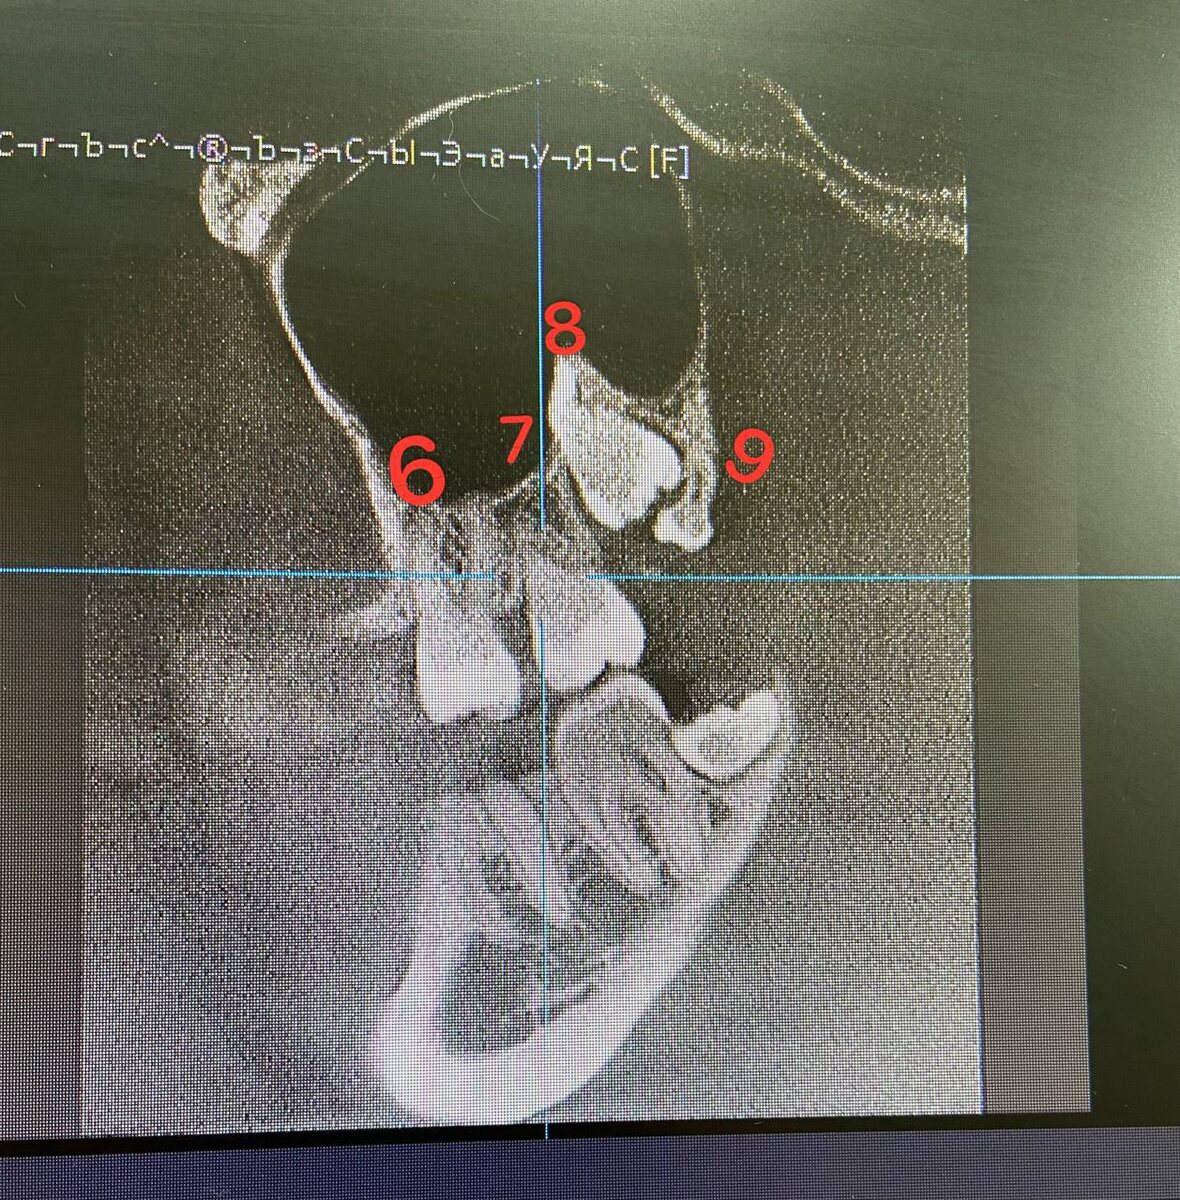

🔺У ЧЕЛОВЕКА, МОЖЕТ БЫТЬ БОЛЬШЕ, ЧЕМ 32 ЗУБА

▫️Это редкость, но все же встречаются 9 зуб 🦷

▪️У пациентки один 9 зуб и в совокупности она имеет 33 зуба 😁

▫️На компьютерной томографии виден этот малыш, 9 зуб🙂